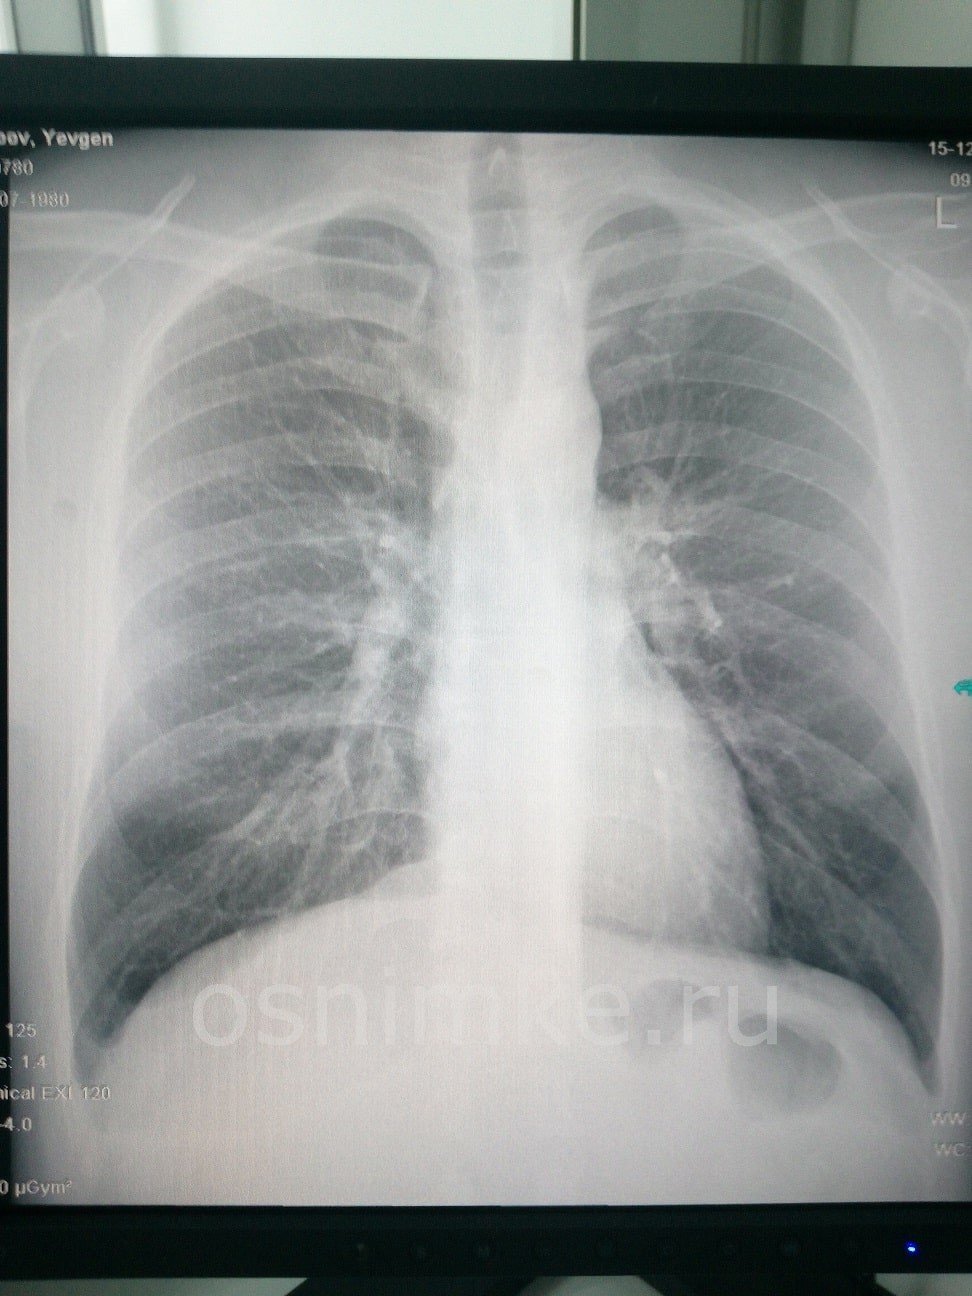

Здравствуйте! Видимой патологии на обзорной рентгенограмме ОГК в прямой проекции не выявлено. Описанные Вами симптомы могут соответствовать остеохондрозу шейного и грудного отделов позвоночника.

- рентгенограмма шейного и грудного отделов позвоночника для начала, хотя-бы в боковых проекциях;

- консультация врача — невролога.